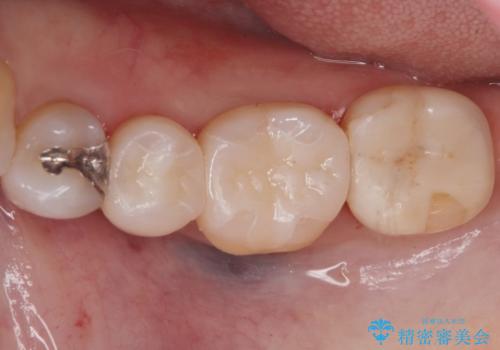

e-maxインレーは銀の詰め物に比べ歯との隙間ができにくく

虫歯の再発リスクが少ないです。

白い詰め物が入り満足して頂けました。